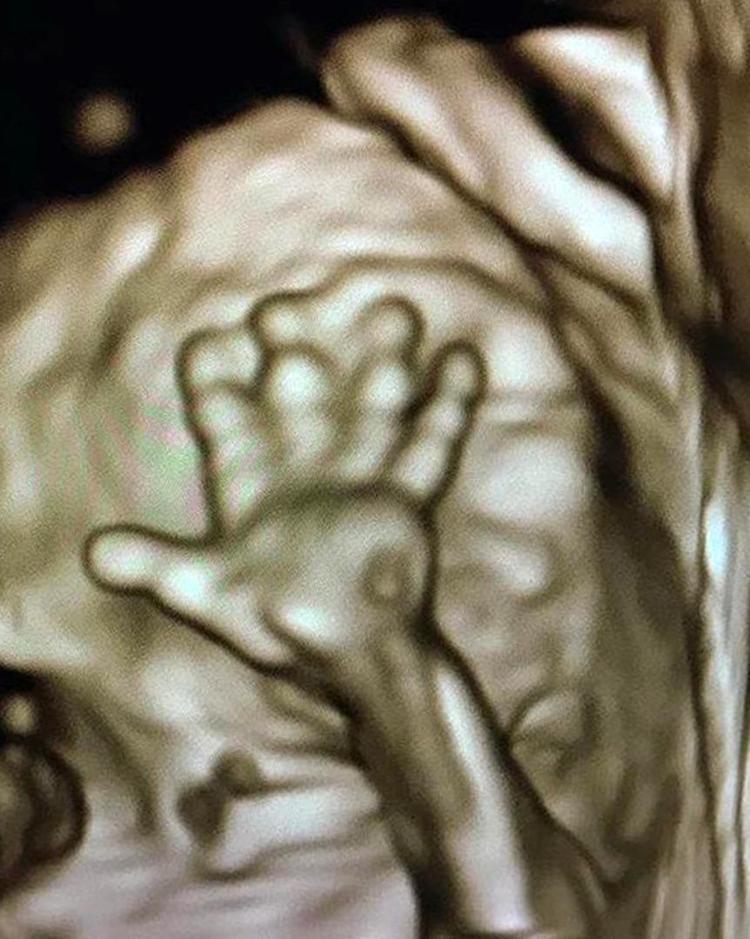

HaberlerFoto Galeri Haberleri Anne karnındaki bebeklerin gülümseten pozları Anne karnındaki bebeklerin gülümseten pozları. • Son Güncelleme: 20 Şubat 2020 - 09:11 • Son Güncelleme: 20 Şubat 2020 - 09:111 23456789101112